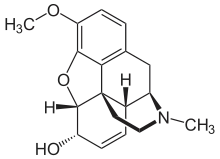

Codeine Codeine |

Codeine-dionine family

Structures

| Codeine-dionine family | ||||

|---|---|---|---|---|

6-Monoacetylcodeine 6-Monoacetylcodeine |

Benzylmorphine Benzylmorphine |

Codeine methylbromide Codeine methylbromide |

Desocodeine Desocodeine |

Dimethylmorphine Dimethylmorphine(6-O-Methylcodeine) |